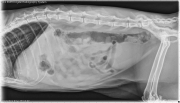

Today we have an 11-year-old male neutered Siamese cat with a history of vomiting. What are your differentials?

R LAT Abdomen

In the abdomen, there is adequate serosal detail. The kidneys are enlarged bilaterally. Nephroliths are present bilaterally with irregular borders. The colon is moderately feces and gas filled. The remainder of the abdomen cavity is within normal limits.

Bilateral renomegaly is suggestive of lymphoma, polycystic kidney disease, inflammatory process, or obstruction. Bilateral nephroliths.

• Polycystic renal disease